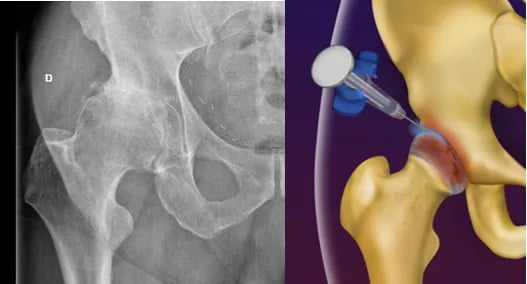

Artrose do Quadril

Apesar de ser uma doença do quadril, alguns pacientes portadores de artrose (desgaste) no quadril podem sentir a dor na coxa, junto com dor no quadril, ou apenas na coxa.

Dessa forma, é importante que caso o exame físico sugira que a dor é oriunda de um problema no quadril, o médico solicite exames do quadril, e não apenas da coxa.

A artrose do quadril é uma condição degenerativa da articulação, que cursa com o desgaste da cartilagem, fazendo com que o paciente apresente dor ao andar e movimentar o quadril.

Faz-se o diagnóstico com RX e Ressonância Magnética.

O tratamento se inicia com medicações analgésicas, perda de peso e Fisioterapia. No entanto, pode-se realizar infiltração com ácido hialurônico na articulação caso o paciente persista com dor na coxa ou dor no quadril.

Com o avanço dos materiais utilizados na cirurgia e nas técnicas cirúrgicas, o paciente volta a ter uma vida normal, praticamente sem limitações após a cirurgia. As próteses mais modernas têm uma durabilidade de aproximadamente 25 anos, permitindo que mesmo pacientes mais jovens possam ser submetidos a essa cirurgia.